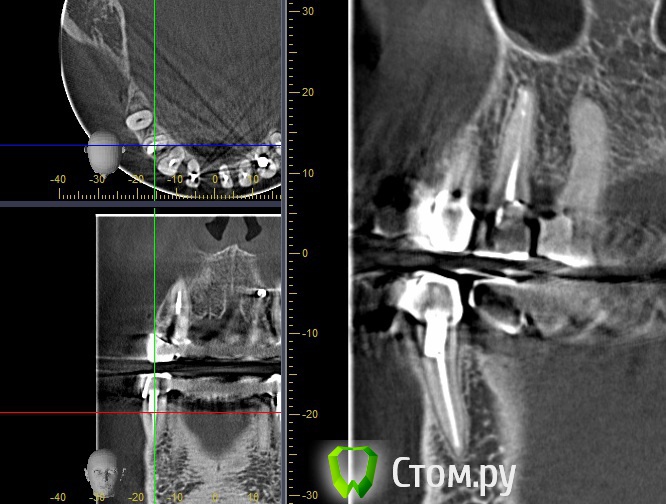

stradalitca Опубликовано 20 мая, 2014 Автор Поделиться Опубликовано 20 мая, 2014 (изменено) Добрый вечер! Я тут ещё глянула как установлен штифт на четвёрке снизу справа. Вот фото в проекциях. Неужели зуб тоже пробит штифтом? или пойдёт ? и я зря переживаю. Изменено 20 мая, 2014 пользователем stradalitca Ссылка на комментарий

Korel Опубликовано 23 мая, 2014 Поделиться Опубликовано 23 мая, 2014 Неужели зуб тоже пробит штифтом? Похоже на то. А Вы не рассматривали для Вашей мамы вариант (на н\чел.) бюгельный протез с замковыми креплениями. 1 Ссылка на комментарий

stradalitca Опубликовано 23 мая, 2014 Автор Поделиться Опубликовано 23 мая, 2014 почитала про мплантанты. Получается, что нам это не особо подходит. Начиная с того, что надо вылечить всю остальную челюсть - то есть убрать очаги воспаления. А воспаление видно невоооружённым глазом. Сегодня у неё стала кровить нижняя четвёрка справа. то ли от полосканий солью, то ли дают знать о себе очередной неудавшийся штифт.А бюгельный протез Вы предлагаете на место моста из 9 коронок и плюс 5,6,7 слева? я правильно поняла? Ссылка на комментарий